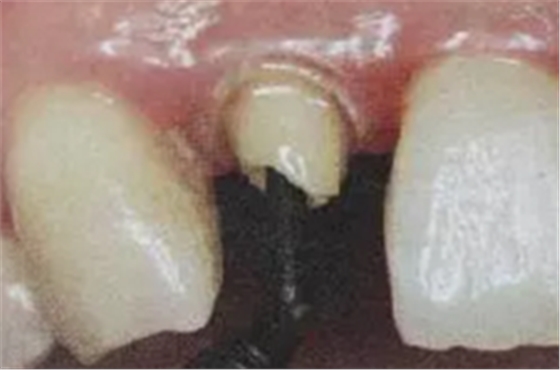

6. 纖維樁的試放和裁戴

纖維樁試放時(shí)應(yīng)用鑷子夾持將其插入預(yù)備的根管樁道中(這涉及無菌觀念和操作),就位時(shí)無阻力可稍有錮住感。

(鑷子夾持(正確))

(污染手套夾持(錯(cuò)誤))

(技工鉗裁剪(錯(cuò)誤))

試放后應(yīng)按所需長(zhǎng)度用細(xì)粒金剛砂車針切割裁剪。

(粘樁堆核固化后裁剪)

為防止裁剪過程中有可能造成樁表面的污染,可以粘結(jié)固位后再進(jìn)行裁剪。